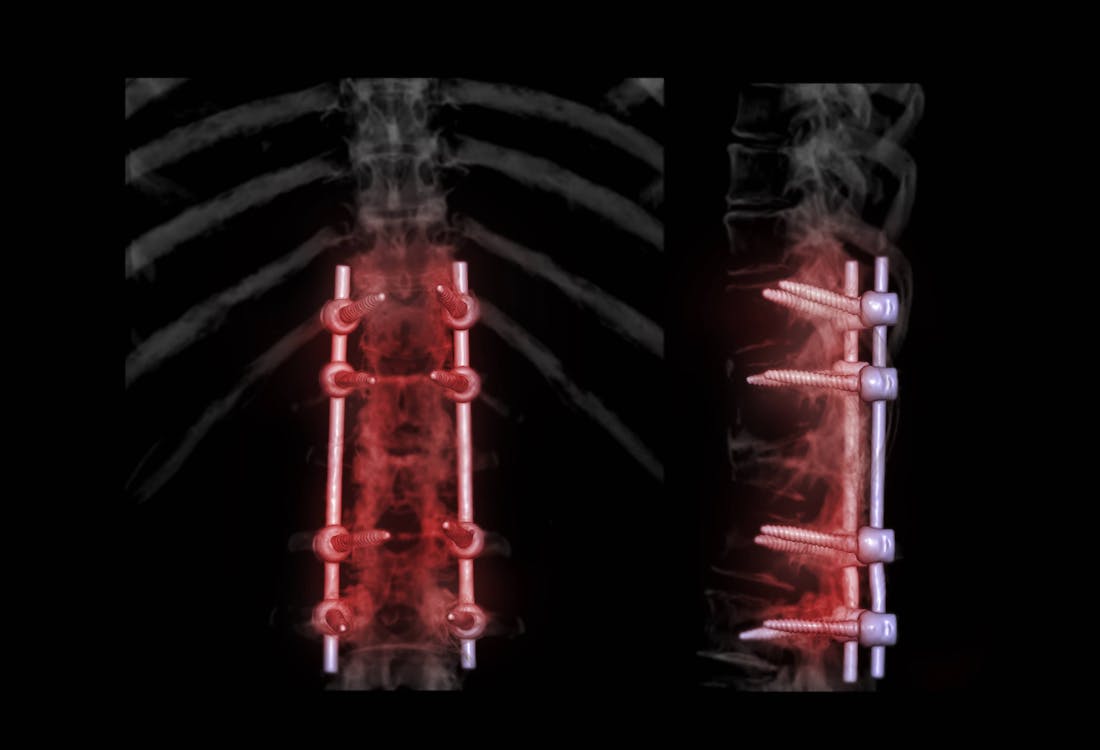

Spinal Fusion

Spinal fusion is a surgical technique that joins (or fuses) one or more of the vertebrae of the spine to stop them from moving against each other. This is done by placing bone grafts or bone graft substitutes between the affected vertebral bone. The graft material acts as a binding medium and helps to maintain normal disc height – as the body heals, the vertebral bone and bone graft eventually grow together to join the vertebrae and stabilize the spine.

Lumbar Interbody Fusion

Our expert team performs both ALIF: Anterior Lumbar Interbody Fusion (with bone graft and metal plate) and XLIF® Lateral Lumbar Interbody Fusion. ALIF is generally used to treat back or leg pain caused by degenerative disc disease. Unlike traditional back surgery, XLIF® is performed through the patient's side. By entering this way, major muscles of the back are avoided. This minimally invasive procedure is generally used to treat leg or back pain caused by degenerative disc disease.